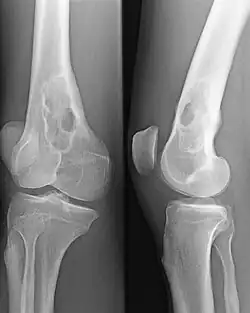

- Auch gelenknahe Knochenzysten stellen Osteolysen dar und treten bei fortgeschrittenen Arthrosen als „Geröllzysten“ und entzündlichen Gelenkerkrankungen, wie der chronischen Polyarthritis auf.